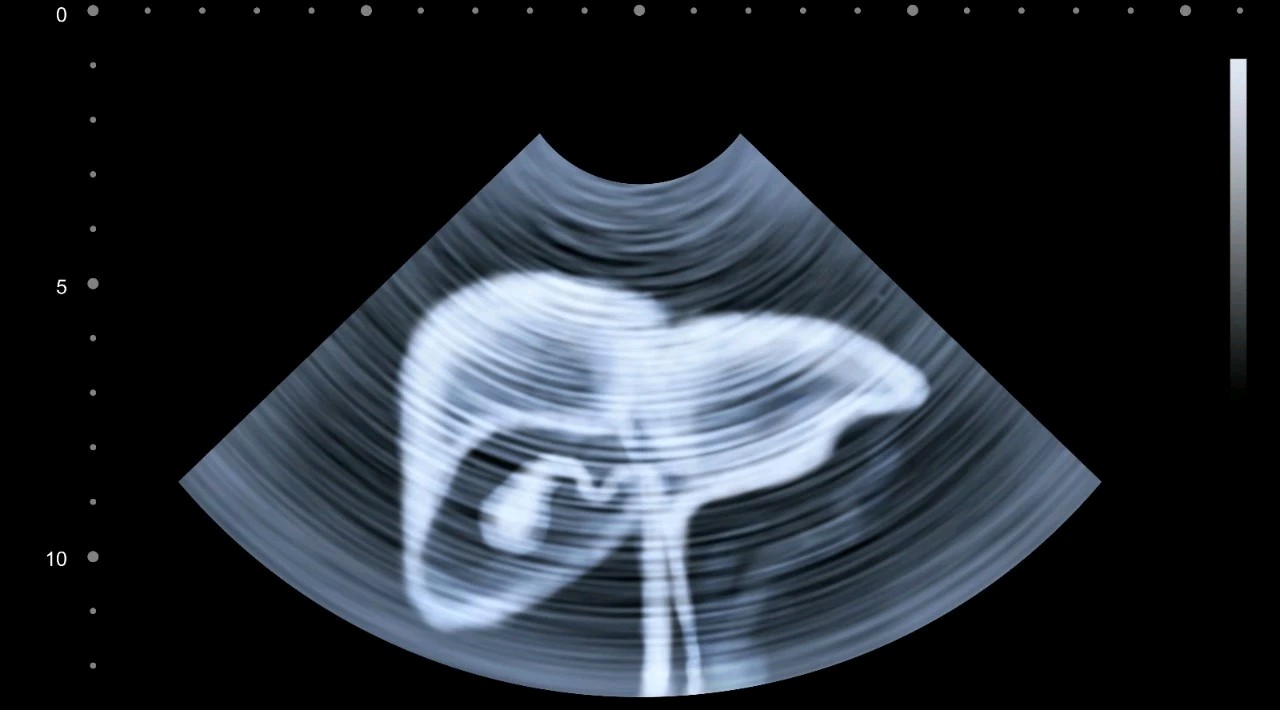

1.如果是前三类人(有乙肝、有肝硬化、家中有肝癌患者):建议每3-6个月做一次腹部B超检查+血清甲胎蛋白(AFP)检查;